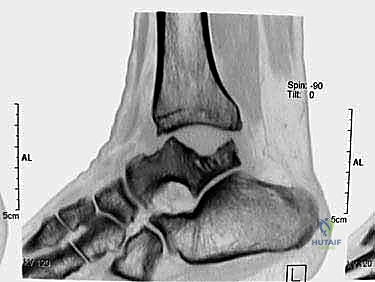

تبدأ رحلة العلاج مع الأستاذ الدكتور محمد هطيف بتقييم شامل. يتم إجراء فحوصات دموية كاملة، وتخطيط للقلب، والأهم من ذلك: التصوير الطبي المتقدم.

يعتمد الدكتور هطيف على الأشعة السينية (X-rays) والأشعة المقطعية (CT Scans) ثلاثية الأبعاد لبناء خريطة دقيقة للتشوهات العظمية وتحديد حجم ومسار المسمار النخاعي المناسب لكل مريض بدقة متناهية. يتم مناقشة كل هذه التفاصيل بشفافية تامة مع المريض.